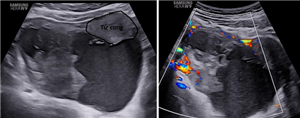

Tăng sinh mạch máu cơ tử cung - thông nối động tĩnh mạch mắc phải

Xem thêm